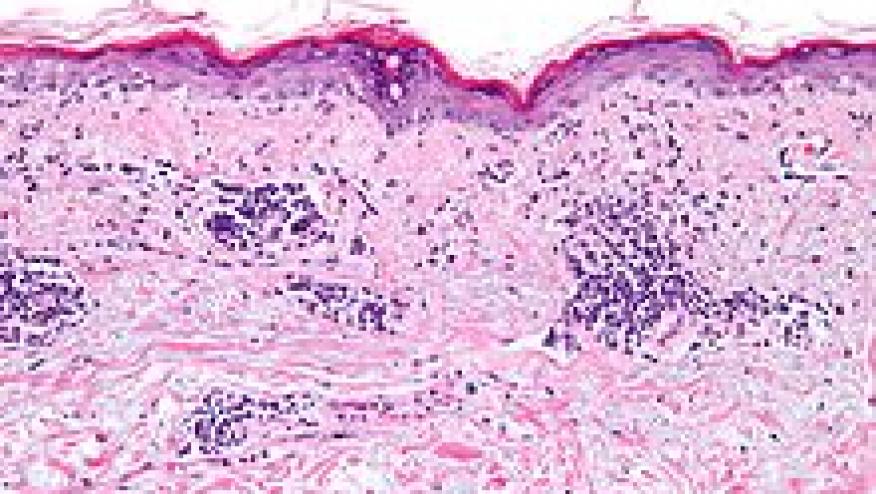

Kahlenberg and coworkers have reported in ARD that interferon kappa (IFN-κ) is a key regulator of type I interferon (IFN) photosensitive responses in patients with cutaneous lupus erythematosus (CLE).

They analyzed mRNA expression of type I IFN gene expression by microarrays of biopsied CLE lesions and healthy control skin. They also examined gene expression in cultured keratinocytes, fibroblasts and endothelial cells IFNK knock-out keratinocytes generated using CRISPR/Cas9.

They discovered that IFNK is one of two type I IFNs significantly increased (1.5-fold change) in lesional CLE skin.

Type I IFN responses were enriched in keratinocytes, but not in fibroblast or endothelial cells, and that epithelial-derived IFN-κ is responsible for maintaining baseline type I IFN responses in healthy skin.